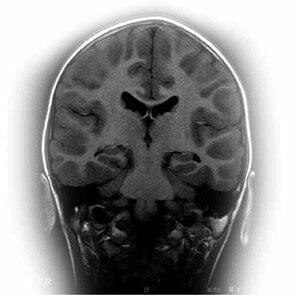

La pregnénolone est produite dans nos surrénales, dans notre cerveau et, également, dans notre système nerveux périphérique où elle pourrait avoir un rôle dans le maintien de la couche de myéline. Elle est également sécrétée dans la peau, les ovaires et les testicules. Elle est le point de départ de la cascade stéroïdienne. Elle est la première hormone à être issue de la transformation du cholestérol. La pregnénolone est un précurseur des minéralocorticoïdes (aldostérone), des glucocorticoïdes (cortisol), de la DHEA et de la progestérone. La pregnénolone et son métabolite le sulfate de pregnénolone sont également synthétisés dans le cerveau, d'où leurs noms de neurostéroïdes. |

L'action de la pregnénolone sur la mémoire a été bien montrée aussi bien chez l'animal que chez l'homme. La pregnénolone est un antagoniste du GABA et un agoniste ou stimulateur des récepteurs NMDA (N-méthyl-D-aspartate) qui renforce le système des neuromédiateurs diminuant avec le vieillissement. La pregnénolone stimule également la synthèse de l'acétylcholine et ceci a été particulièrement bien démontré dans l'hippocampe. |

Aujourd'hui, cette molécule qui est la véritable “ mère ” de toutes les hormones stéroïdes nous intéresse tout particulièrement pour son rôle dans les processus de la mémoire. La pregnénolone qui est un neurostéroïde a une action toute particulière sur notre cerveau. Elle a notamment une action stimulante sur le cerveau et les performances cérébrales sans pour autant avoir cet effet désagréable d'excitation non maîtrisée que l'on obtient avec des surconsommations de vitamine C ou de caféine. Cette action peut naturellement se comprendre quand on sait que les concentrations intracérébrales de pregnénolone sont dix fois supérieures à celles de la DHEA, alors que cette dernière reste le stéroïde le plus important du corps humain. |

En revanche, les effets de la pregnénolone deviennent particulièrement intéressants pour la mémoire chez les personnes de plus de 50 ans. La pregnénolone est une des substances naturelles les plus actives pour stimuler et améliorer la mémoire chez l'animal. La pregnénolone bloque les effets inhibiteurs de l'acide aminé glycine et du GABA contribuant à l'équilibre de la balance inhibition / excitation du système nerveux central. Elle augmente le relargage de l'acétylcholine, puissant neuromédiateur, et agit sur les récepteurs NMDA (N-méthyl-D-aspartate) impliqués dans la mémoire. |

Il est d'ailleurs particulièrement intéressant de remarquer que l'acétylcholine et les glutamates sont directement impliqués dans la maladie d'Alzheimer qui se révèle par une atteinte de la mémoire à court terme. La pregnénolone est environ 100 fois plus efficace sur la mémoire que les autres stéroïdes. Au-delà de cet effet sur la mémoire, elle agit également sur le bien-être, sur le stress et la fatigue qu'il induit. |